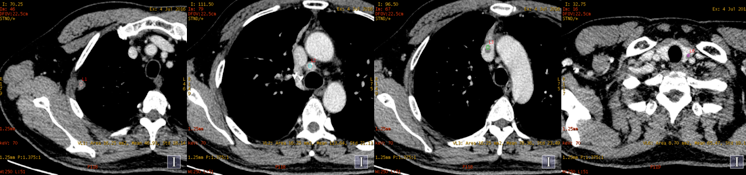

能谱平扫及两期增强扫描。病理已提示右上肺癌纵隔淋巴结转移;上腔静脉病灶为癌栓?血栓?左甲状腺病灶为转移?原发病灶?

常规图像及碘基图均显示上腔静脉病灶明显强化。